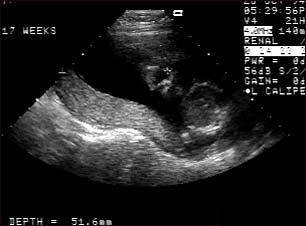

Ecografia fetala